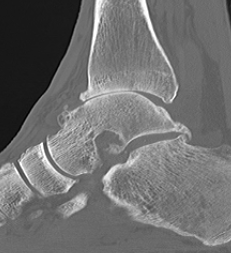

CT

Evaluate bone stock to determine if TAR is appropriate